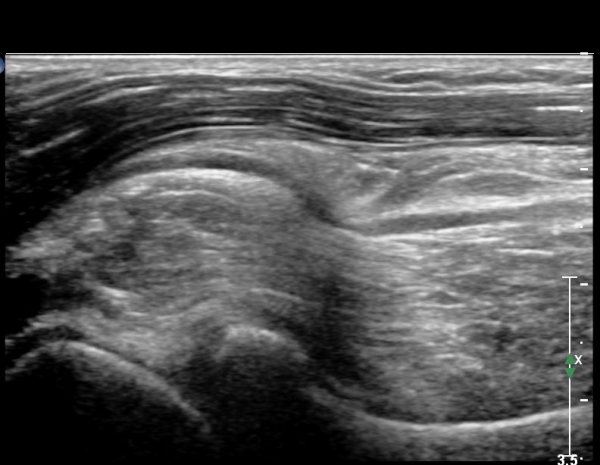

ÆÈ²ÞÄ¡ ¾Õ Á¾´Ü¸é°Ë»ç¿¡¼­ ÀÌÁú¼º °í¿¡ÄÚ Á¾±«´Â  ȸ¿Ü±ÙÀ» ħ¹üÇÏ¿© ÆÛÁ®ÀÖÀ¸¸ç   Èİñ°£½Å°æÀÇ Àü¹ÝÀûÀÎ ºÎÁ¾°ú

±¹¼ÒÀû ¾Ð¹ÚÀÌ °üÂûµÊ(»çÁö 4).